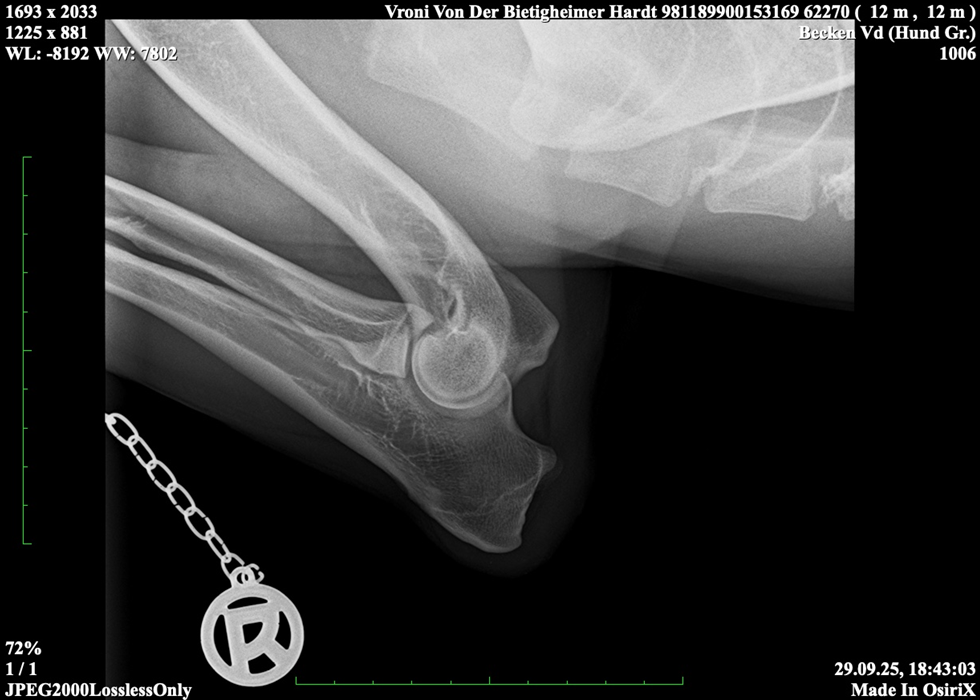

Vroni von der Bietigheimer Hardt

SZ. 2395403; WT: 27.09.2024;

HD ZW: kW25/02 „69“ Größen-ZW: kW25/02 „101!